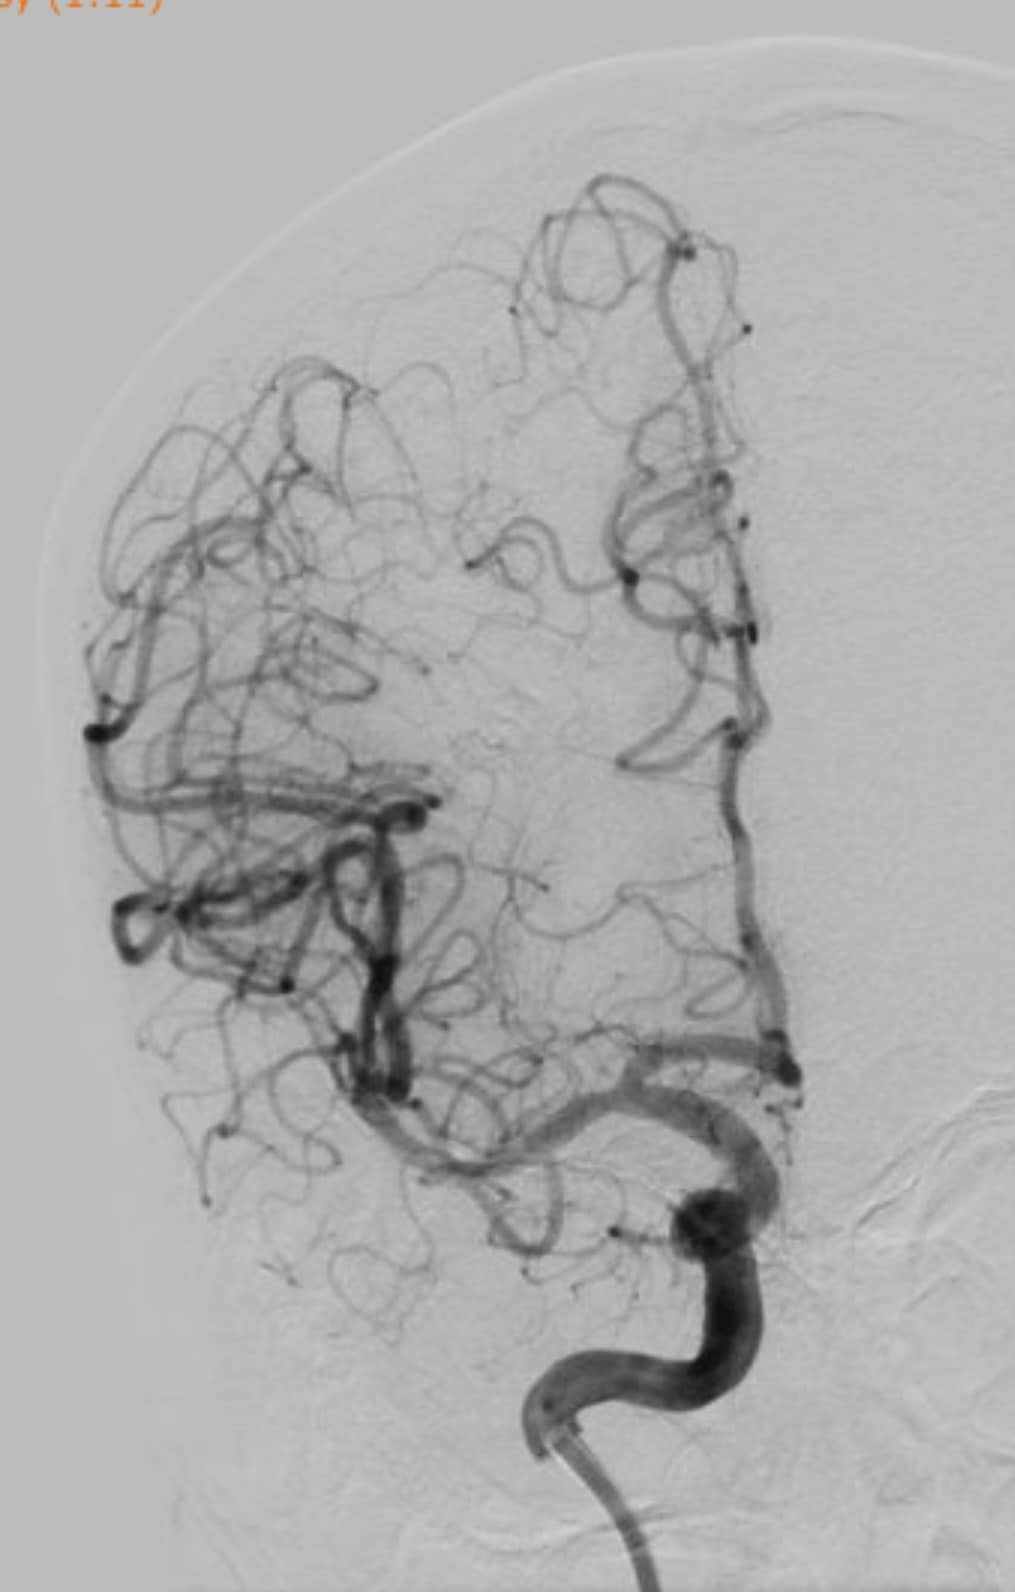

Theo đó, các bác sĩ đã quyết định bỏ qua rtPA đường tĩnh mạch và chuyển thẳng cho bác sĩ can thiệp. Sau khoảng 60 phút, các bác sĩ lấy ra được một mảng sùi kèm huyết khối và tái thông hoàn toàn động mạch não giữa. Đến ngày hôm sau, bệnh nhân đã phục hồi gần hoàn toàn.

Sau khoảng 60 phút, các bác sĩ lấy ra được một mảng sùi kèm huyết khối và tái thông hoàn toàn động mạch não giữa cho bệnh nhân. (Ảnh: BVCC)